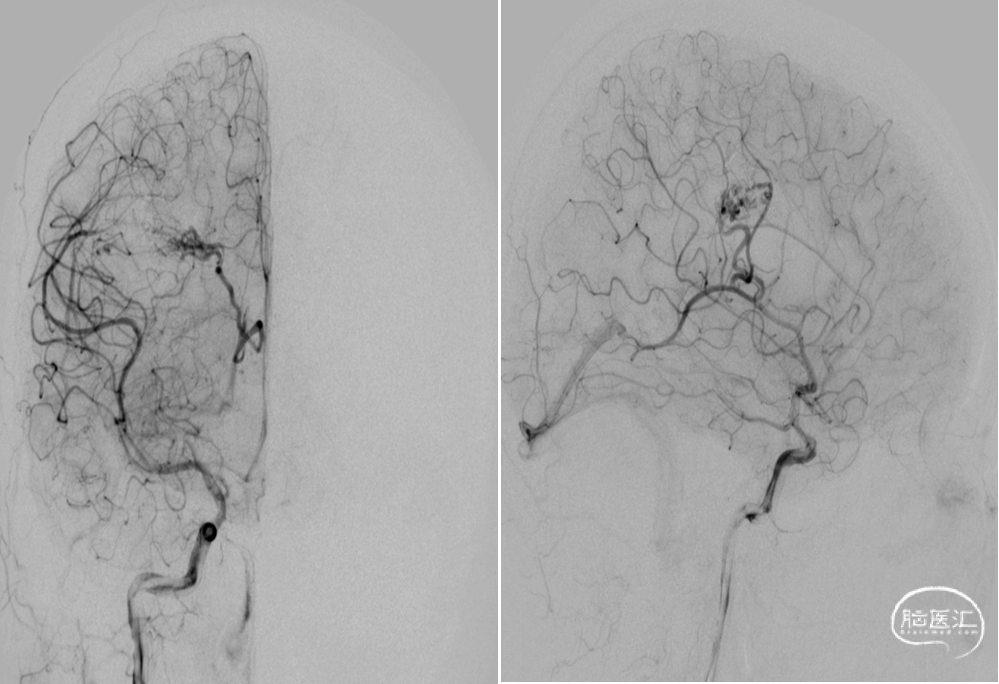

DSA:右侧额顶叶脑动静脉畸形

15%外科胶做塞子,注射Onyx18栓塞